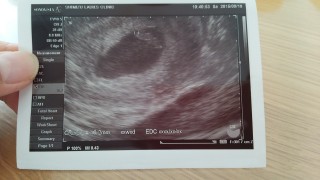

体外受精(凍結胚移植5日目胚盤胞)で授かりました。 D28/BT10妊娠判定hCG691。 5w5d胎嚢確認GS16.7mm。 7w2d心拍・心音確認CRL12.4mm。 たくましくドックンドックン動く心音を聞かせてもらって感動しました。 母子手帳も貰い8w2dにクリニック卒業です。